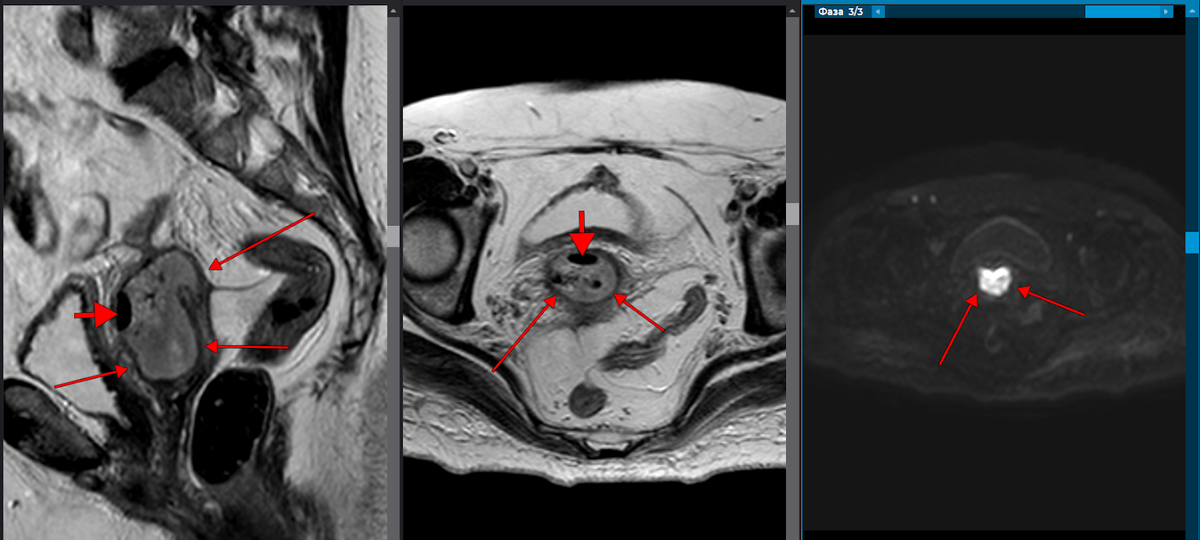

In its purest form, the ovarian remnant manifests as a cyclically painful, unilateral adnexal mass that is palpable on bimanual pelvic examination and can be visualized by transvaginal ultrasound, magnetic resonance imaging (MRI), or computed tomography (CT) scan. Premenopausal levels of FSH and estrogen demonstrate continued ovarian function.